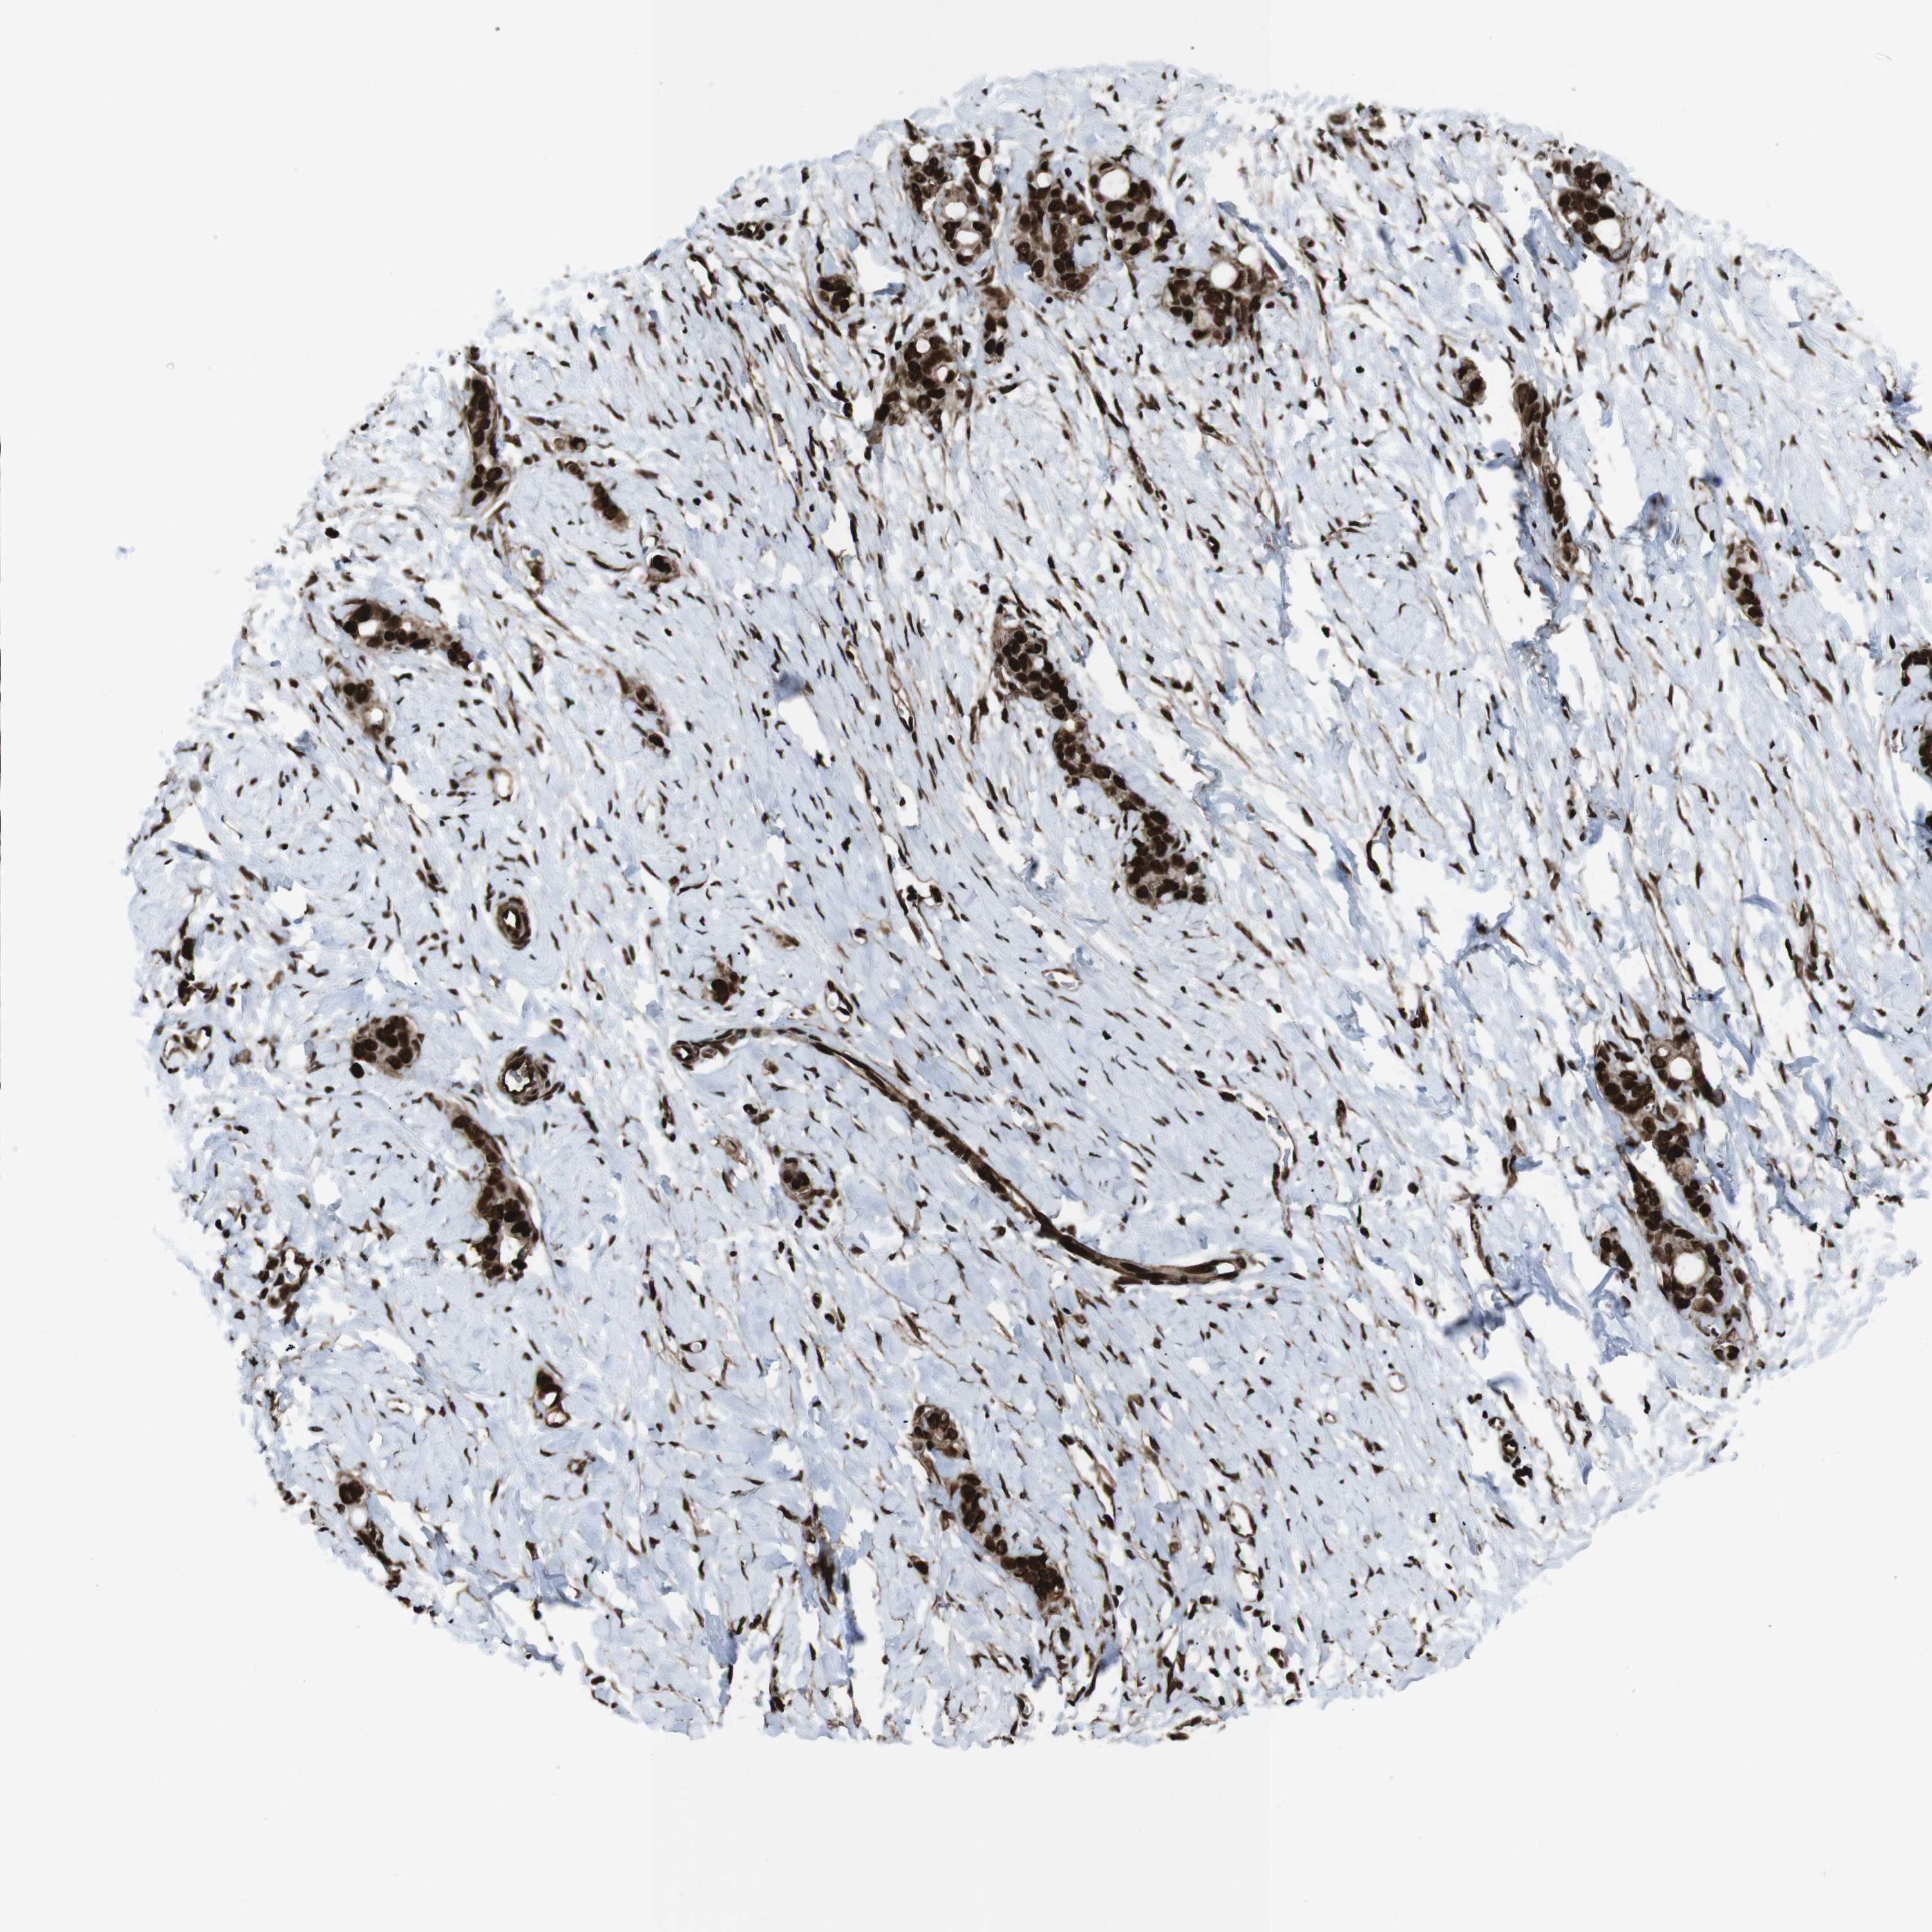

STOMACH CANCER - Protein expressioni

A mouse-over function shows sample information and annotation data. Click on an image to view it in a full screen mode. Samples can be filtered based on level of antibody staining by selecting one or several of the following categories: high, medium, low and not detected. The assay and annotation is described here.

Note that samples used for immunohistochemistry by the Human Protein Atlas do not correspond to samples in the TCGA dataset.

Antibody stainingi

Antibody staining in the annotated cell types in the current human tissue is reported as not detected, low, medium, or high, based on conventional immunohistochemistry profiling in selected tissues. This score is based on the combination of the staining intensity and fraction of stained cells.

Each image is clickable and will lead to virtual microscopy that enables deeper exploration of all samples and also displays staining intensity scores, fraction scores and subcellular localization as well as patient and tissue information for each sample.

Antibody HPA041057

Antibody HPA058707

Antibody CAB011532

Staining

High

Medium

Low

Not detected

Intensity

Strong

Moderate

Weak

Negative

Quantity

>75%

75%-25%

<25%

None

Location

Nuclear

Cytoplasmic/membranous

Cytoplasmic/membranous,nuclear

Adenocarcinoma, NOS

Adenocarcinoma, High grade